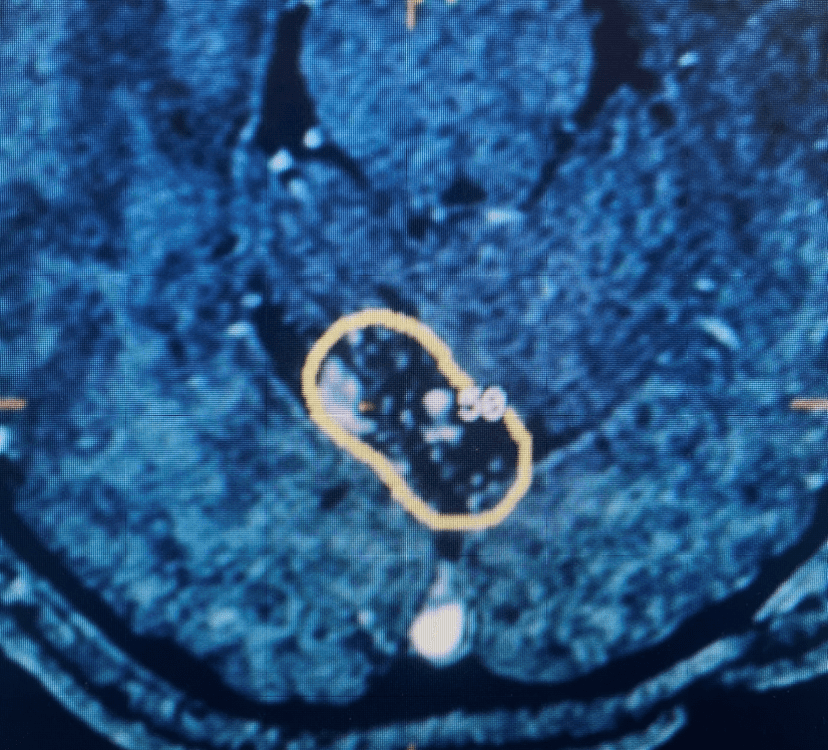

This is a 57-year-old woman with new onset memory problems and gait difficulty. MRI demonstrated a 3 cm tumor in the pineal region, most consistent with […]

Collateral venous drainage into the orbit and skull base was observed (Fig. A). After successful cannulation of the direct aperture between the right carotid artery and […]